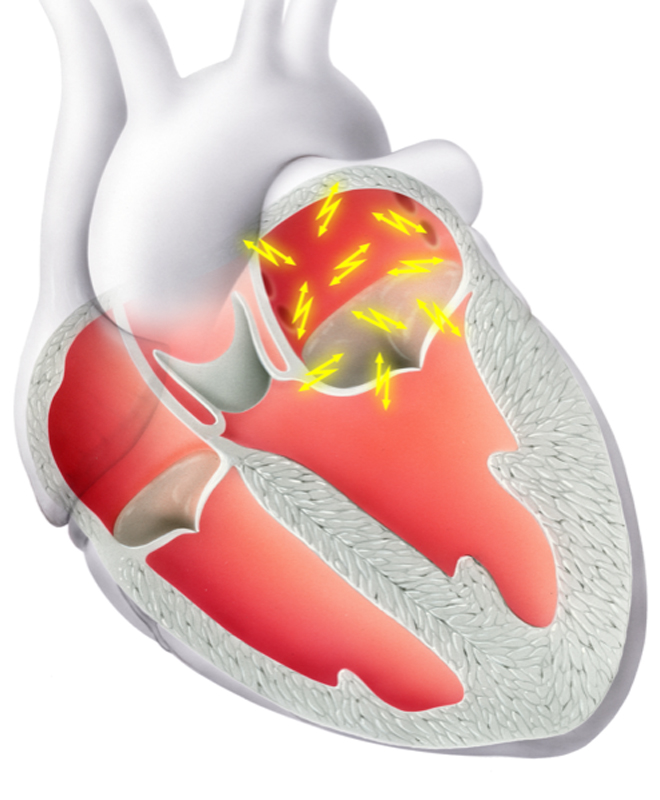

Eine bewährte Therapie bei verschiedensten Herzrhythmusstörungen, insbesondere wenn eine Rhythmuskontrolle erzielt werden soll, ist die Ablation mittels Spezialkatheter. Hierfür werden im Rahmen einer elektrophysiologischen Untersuchung (EPU) verschiedene Orte auf der Herzinnenseite, die für die Rhythmusstörungen verantwortlich sind, aufgesucht. Anschliessend wird die Elektrode des Katheters mit Hochfrequenzstrom erhitzt oder mittels Kälteabgabe angefroren. Die erzeugten Läsionen haben zum Ziel die Ausbreitung der elektrischen Impulse einzuschränken und somit die Rhythmusstörung zu eliminieren.

Eine bewährte Therapie bei verschiedensten Herzrhythmusstörungen, insbesondere wenn eine Rhythmuskontrolle erzielt werden soll, ist die Ablation mittels Spezialkatheter. Hierfür werden im Rahmen einer elektrophysiologischen Untersuchung (EPU) verschiedene Orte auf der Herzinnenseite, die für die Rhythmusstörungen verantwortlich sind, aufgesucht. Anschliessend wird die Elektrode des Katheters mit Hochfrequenzstrom erhitzt oder mittels Kälteabgabe angefroren. Die erzeugten Läsionen haben zum Ziel die Ausbreitung der elektrischen Impulse einzuschränken und somit die Rhythmusstörung zu eliminieren.

Typische Herzrhythmusstörungen, welche mittels Ablation behandelt werden können, sind:

- Vorhofflimmern (Abb 1 und 2)

Eine bewährte Therapie bei verschiedensten Herzrhythmusstörungen, insbesondere wenn eine Rhythmuskontrolle erzielt werden soll, ist die Ablation mittels Spezialkatheter. Hierfür werden im Rahmen einer elektrophysiologischen Untersuchung (EPU) verschiedene Orte auf der Herzinnenseite, die für die Rhythmusstörungen verantwortlich sind, aufgesucht. Anschliessend wird die Elektrode des Katheters mit Hochfrequenzstrom erhitzt oder mittels Kälteabgabe angefroren. Die erzeugten Läsionen haben zum Ziel die Ausbreitung der elektrischen Impulse einzuschränken und somit die Rhythmusstörung zu eliminieren.

Typische Herzrhythmusstörungen, welche mittels Ablation behandelt werden können, sind:

- Vorhofflimmern (Abb 1 und 2)